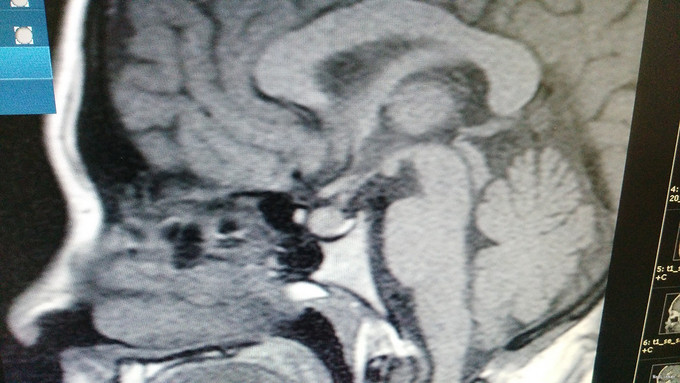

入院查体:无毛发增多,无满月脸及多血质面容,齿龈有色素沉着,可见喉结,颜面及后背可见皮肤痤疮,毛囊角化,未见明显胡须及腋毛,无颈蹼、肘外翻、双乳腺未发育。腹部未见紫纹,阴毛稀少、呈女性分布,可见阴蒂肥大呈阴茎状,外阴部仍可见尿道口。 入院后完善检查及检验: 肾上腺皮质节律: 8:00 15:00 24:00 第一天:ACTH 15.82 18.8 172.6 COR 277.6 372.7 387 第二天:ACTH 29.98 17.51 6.97 COR 478.7 227.4 57.66 第三天:ACTH 42.35 13.15 12.52 COR 547.9 179.3 62.07 血清生长激素测定GRH<0.15mIU/L。胰岛素生长样因子-1IGF-1183.00ng/ml。血清泌乳素测定PRL350.00mIU/L。促性腺激素系列:血清促卵泡刺激素测定FSH3.36mIU/mL,血清促黄体生成素测定LH9.47mIU/mL。男性激素系列:血清雄烯二酮测定AND10.80nmol/L,血清睾酮测定TES3.50nmol/L,血清游离睾酮F-TEST12.13pmol/L,血清脱氢表雄酮及硫酸酯测定DHS5.89umol/L,性激素结合球蛋白SHBG54.20nmol/L。雌性激素系列:血清孕酮测定PRG6.77nmol/L,血清雌三醇测定UE3<0.24nmol/L,血清雌二醇测定E2354.00pmol/L。阴式彩超:右卵巢囊性回声,内呈网状,盆腔积液。鞍区MR平扫+增强:垂体形态饱满,考虑垂体增生,请结合临床。肾上腺3D增强CT:左侧肾上腺结合部改变